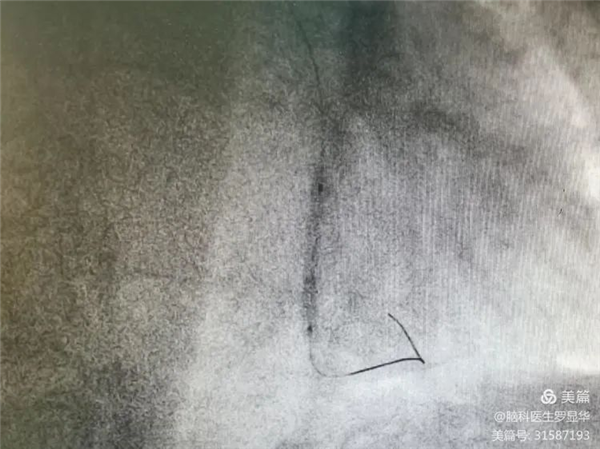

釋放冠脈球擴(kuò)支架Xbg安康新聞網(wǎng)